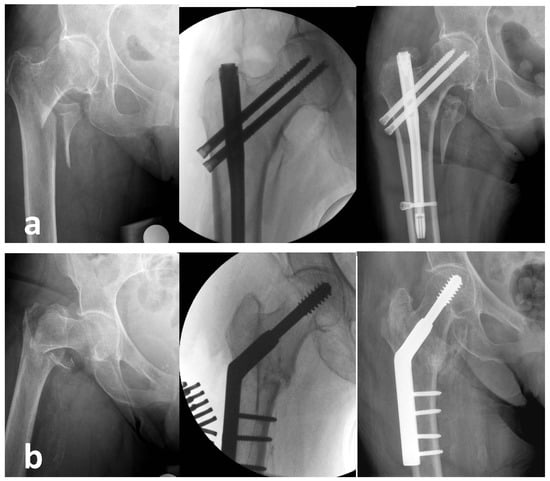

Endovis Nail versus Dynamic Hip Screw for Unstable Pertrochanteric Fractures: A Feasibility Randomised Control Trial including Patients with Cognitive Impairment

| Radiographic Results | Nail (n = 29) | DHS (n = 28) | Mean Difference (95% Confidence Interval) | p-Value |

|---|---|---|---|---|

| TAD (mm), mean ± SD | 18.2 ± 6.8 | 14.9 ± 4.3 | 3.2 (0.1, 6.4) | 0.044 |

| Neck collapse (mm), mean ± SD | ||||

| Week 2 | 1.19 ± 2.2 | 9.5 ± 8.6 | −8.3 (−12.2, −4.4) | <0.001 |

| Week 4 | 3.4 ± 4.0 | 10.6 ± 8.1 | −7.2 (−11.1, −3.3) | 0.001 |

| Week 12 | 2.9 ± 3.5 | 12.2 ± 9.4 | −9.4 (−14.0, −4.8) | 0.001 |

| Medial displacement >5 mm, n (%) | ||||

| 2 weeks | 4 (16%) | 15 (53.6%) | 0.009 | |

| 4 weeks | 3 (13%) | 16 (61.5%) | 0.001 | |

| 12 weeks | 2 (9.5%) | 15 (62.5%) | <0.001 | |

| Shortening (mm), mean ± SD | ||||

| Week 2 | 5.1 ± 5.7 | 9.8 ± 9 | −4.7 (−8.9, −0.4) | 0.032 |

| Week 4 | 5.2 ± 6 | 12.1 ± 9.5 | −7 (−11.5, −2.4) | 0.004 |

| Week 12 | 6.8 ± 7 | 12.2 ± 8.6 | −5.4 (−10.2, −0.6) | 0.029 |

| RUSH 12 weeks, mean ± SD | 22.9 (5.7) | 24.5 (4.4) | −1.7 (−4.8, 1.4), n = 45 | 0.277 |